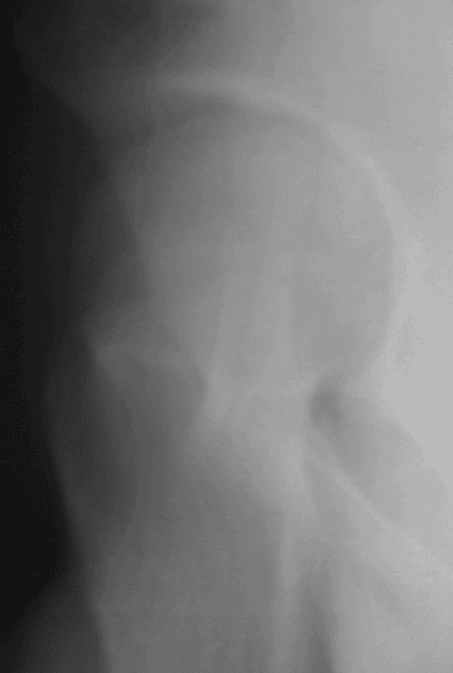

Уважаемые коллеги! Заканчивая обследование больного с переломо-вывихом бедра сделал ему обычные R-томограммы. Кажется удалось "поймать" и отломок и донорское место. Мои выводы - в скиаграмме. Считаю, что это передне-нижний фрагмент головки, образовавшийся вследствии отрывного перелома. На томограммах отломок обозначаю длинной стрелкой, а место откуда он оторвался - более короткой. Учитывая тот факт, что его размеры по КТ 25 х 15 мм считаю, что его фиксация на место необходима для профилактики артроза, что при 16-ти летнем возрасте пациента важно в плане максимального отодвигания эндопротезирования. Планирую оперировать его 24.05.05 г. Результаты представлю.

Прямой при поступлении

Прямой 19.05

Несколько соображений к "картинкам". На прямом снимке и КТ-томограммах все типичные линии вертлужной впадины: крыша, передняя стенка, задняя стенка - сохранены. На КТ-сканах 6 и 7 появляется фрагментация головки. С учетом R-томограмм отломок расположен спереди-снизу, а не сзади-сверху от сустава, как написано в описании КТ.